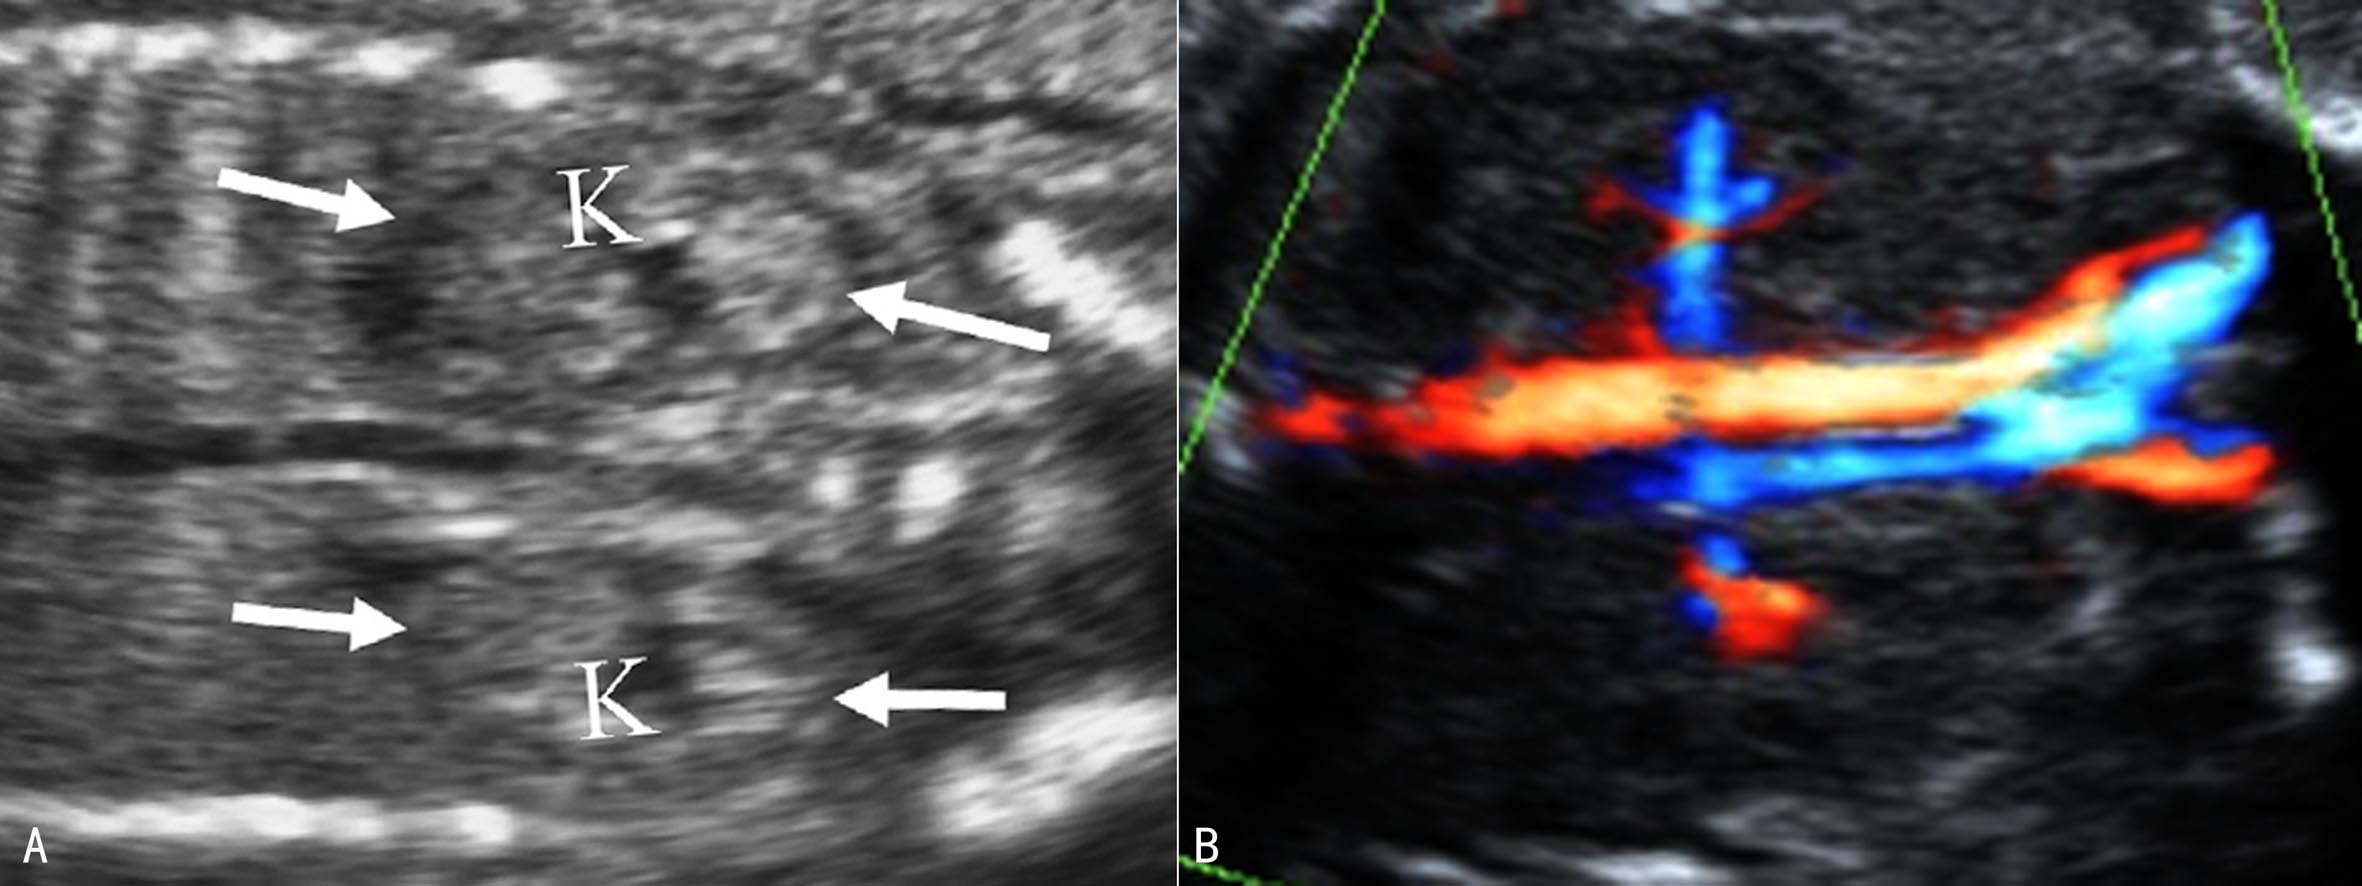

1.肾脏 孕14周时可显示出胎儿双肾,18周后可清晰显示(图5)。正常肾脏位于脊柱两旁,低于成人肾的位置,在腹部脊柱旁矢状面上呈长圆形蚕豆样,肾脏水平横切时呈圆形,右侧(RK)稍低于左侧(LK)。最初胎儿肾脏为均匀的低回声区结构。随着妊娠的进展,可见到更为详细的内部结构。等回声的肾皮质包绕在低回声的锥形髓质周围,中央强回声区为集合系统,肾盂呈无回声长条状结构,位于集合系统中央。肾外周为肾周脂肪和肾囊。当超声显像检查肾脏回声显示不清时,CDFI检查肾动脉有助于确认肾脏的存在(图6)。肾脏周长、容积、厚度和长度均与孕龄有良好的相关性,正常肾脏长度相当于4~5个椎体的高度;在整个妊娠期肾周长/腹围保持在比较恒定的0.27~0.30之间。